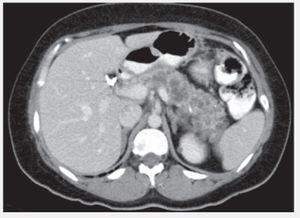

Figura 2. Quistes pancreáticos y renales.

Abdomen globoso, a expensas de panículo adiposo, no adenomegalia, no se palpan masas, dolor a la palpación en epigastrio. Glucosa: 76 mg/dL, Creatinina: 0.87 mg/dL, amilasa y lipasa normales, TC abdomen: Lesiones quísticas de páncreas y ambos riñones. IRM Abdomen: Lesiones quísticas en páncreas y ambos riñones. IRM de cerebro: Hemangioblastoma en cerebelo.